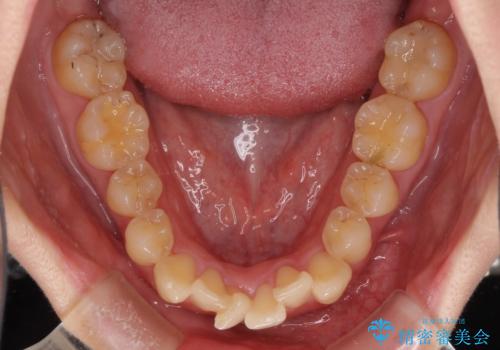

上下前歯のデコボコをきれいに インビザラインによる矯正治療

- 前歯の著しい叢生と前突感を気にして来院された患者様です。

叢生が強いため、事前に前歯をワイヤー矯正で速やかに叢生を解消し、その後はインビザラインにて矯正治療を行うこととしました。

ワイヤー矯正を併用したことで前歯の叢生を速やかに解消することができました。

一方口元の突出感を改善するために時間がかかり、2年超を要しましたが、満足のいく仕上がりとなりました。